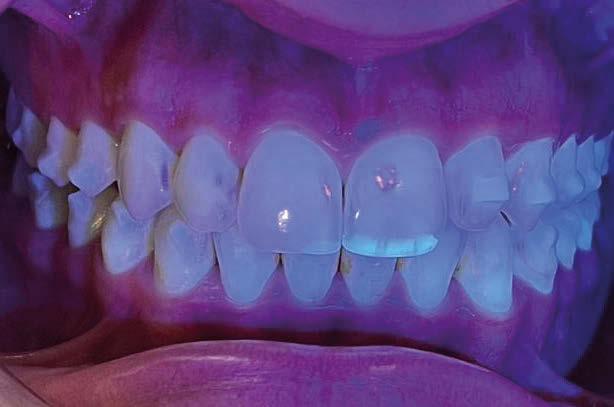

El paciente pediátrico con enfermedad asmática es una problemática diaria en Odontopediatría. Tanto las características propias de la enfermedad como sus repercusiones bucodentales, se deben tener en cuenta para individualizar a cada paciente y buscar su salud oral. Son pacientes con mayor susceptibilidad a caries, gingivitis o erosión dental, entre otras consecuencias debidas a su farmacoterapia. Por ello, es importante que los profesionales de la salud tengan conocimiento para tomar medidas preventivas sobre su higiene oral. De tal forma, la segunda parte de este trabajo (accede al QR para ver la primera parte) tiene la finalidad de presentar una puesta al día sobre la enfermedad asmática y sus manifestaciones clínicas y orales, así como la manera de actuar ante una crisis asmática durante el tratamiento dental. Así pues, se va a realizar una revisión bibliográfica

con el fin de actualizar el protocolo en la consulta dental con pacientes asmáticos y, de esta manera, poder reducir su problemática dental.

Tras los resultados obtenidos llegaron a la conclusión de que son muchas las patologías asociadas al asma, y no solo repercusiones sobre su salud oral, sino maloclusiones del tipo mordida abierta o paladar ojival asociadas a deglución atípica, propias de una respiración oral

también relacionada con esta patología. El pH ácido se encontró en un 96,42% de los niños y se sabe que tiene relación directa con la formación de caries. No encontraron asociaciones con xerostomía, erosión dental o candidiasis, siendo estas patologías relacionadas, al mismo tiempo, con la inmunosupresión generada por los fármacos (1).

Domenzain-Sanchez y cols. realizaron un estudio transversal de casos y controles con pacientes de 5 a 12 años. Un 80% de los asmáticos presentaban caries, a pesar de que los autores no encontraban relación directa entre caries y enfermedad asmática. Éstos consideran que la medicación es la causa principal de las caries, ya que gran parte se queda en la orofaringe, además de reducir el flujo salival y tener azú cares. Los niños asmáticos tienen 1,02 mayor riesgo de erosión dental que los niños no asmáticos; esto se debe a la acidez de los fármacos que reducen el pH y provocan reflujo gastroesofágico. La mayoría de los estudios no avalan una asociación directa con el bruxismo, ya que en niños es muy frecuente, pero concretamente

en este estudio resultó que un 14% presentaban bruxismo dentro del grupo de asmáticos y lo justifican con la obstrucción parcial prolongada o completa de las vías respiratorias (53).

La respiración bucal es muy frecuente en niños con asma y surge como una función adaptativa, ya que tienen dificultad respiratoria. Puede implicar cambios de postura a nivel cervical, afectando al crecimiento del niño; además de alteraciones en el crecimiento de maxilares y en los m ú sculos orofaciales, la posición baja de la lengua detiene el crecimiento transversal, originando paladar ojival y mordida cruzada posterior. A nivel anterior, la alteración en la posición lingual provoca deglución atípica.